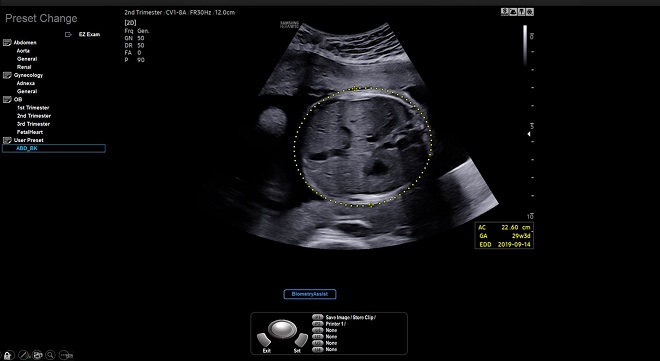

삼성메디슨이 발표한 바이오메트리어시스트(BiometryAssist)는 ‘인텔 코어 i3 프로세서’와 ‘인텔 오픈비노 디스트리뷰션’, ‘오픈CV 툴킷’을 적용해 자동으로 쉽게 태아의 성장 상태를 측정할 수 있다.

▲바이오메트리어시스트(BiometryAssist) 프로그램 화면

바이오메트리어시스트는 클릭 한번으로 약 85 밀리초(ms) 만에 97%의 정확도로 태아 성장 측정이 가능하다. 이러한 자동 측정은 정확한 측정 결과를 일관되게 제공함으로써 의료진이 환자 상담에 더 많은 시간을 할애할 수 있을 것으로 기대한다.